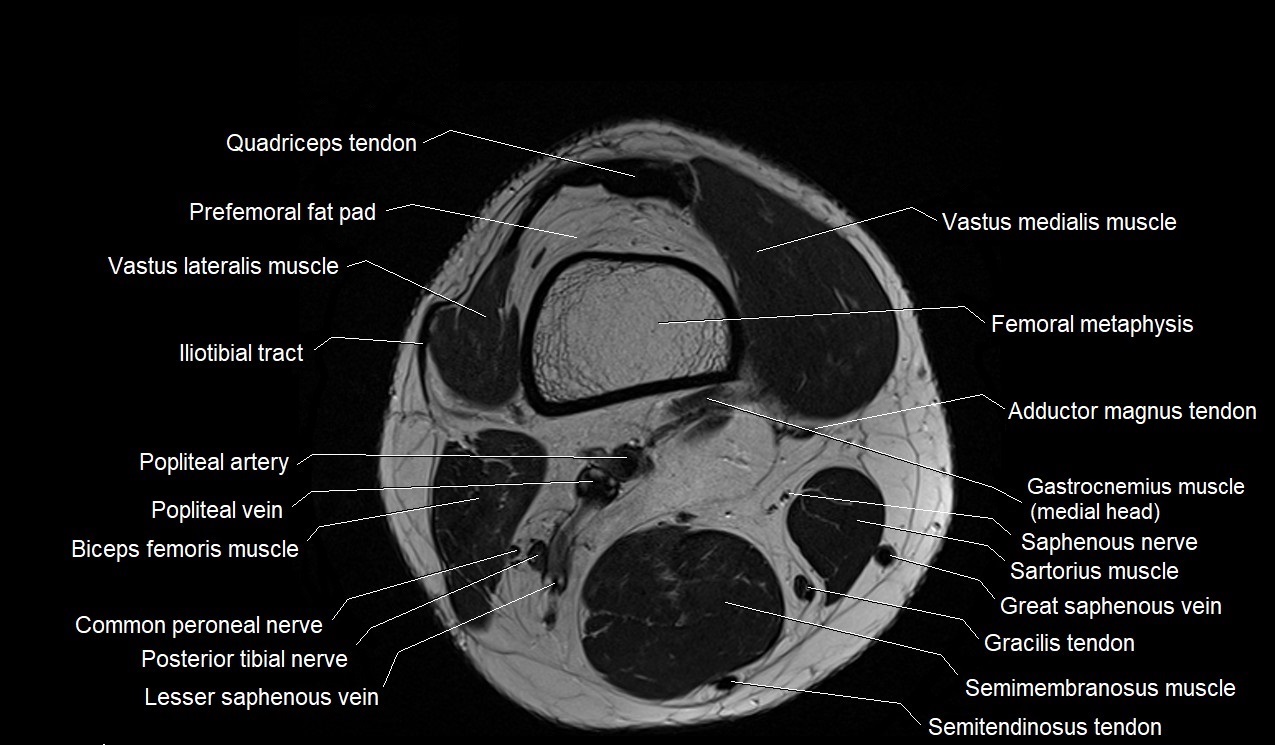

MRI knee axial cross sectional anatomy

Interactive MRI knee axial anatomy viewer for studying cross sectional radiology anatomy of the knee.